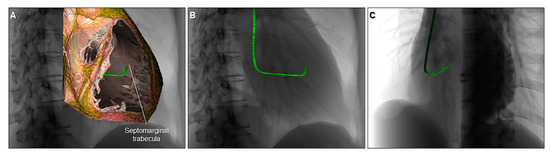

6. Clinical Implication in Congenital Heart Disease with Representative Cases